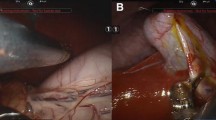

At necropsy, assessments showed that the majority of pigs had recovered well, with port sites healing, and surrounding organs appeared macroscopically healthy with no signs of injury, infection or inflammation (Fig. 5). A single loose clip was found in the abdominal cavity attached to the parietal peritoneum of one pig that underwent cholecystectomy.

Necropsy findings from recovery pigs. A Necropsy of a cholecystectomy recovery pig showing macroscopic evidence of a healthy normal liver and good healing of the cystic duct and artery. B Necropsy of a small bowel enterotomy recovery pig showing no evidence of adhesions and bowel throughout looking healthy and normal